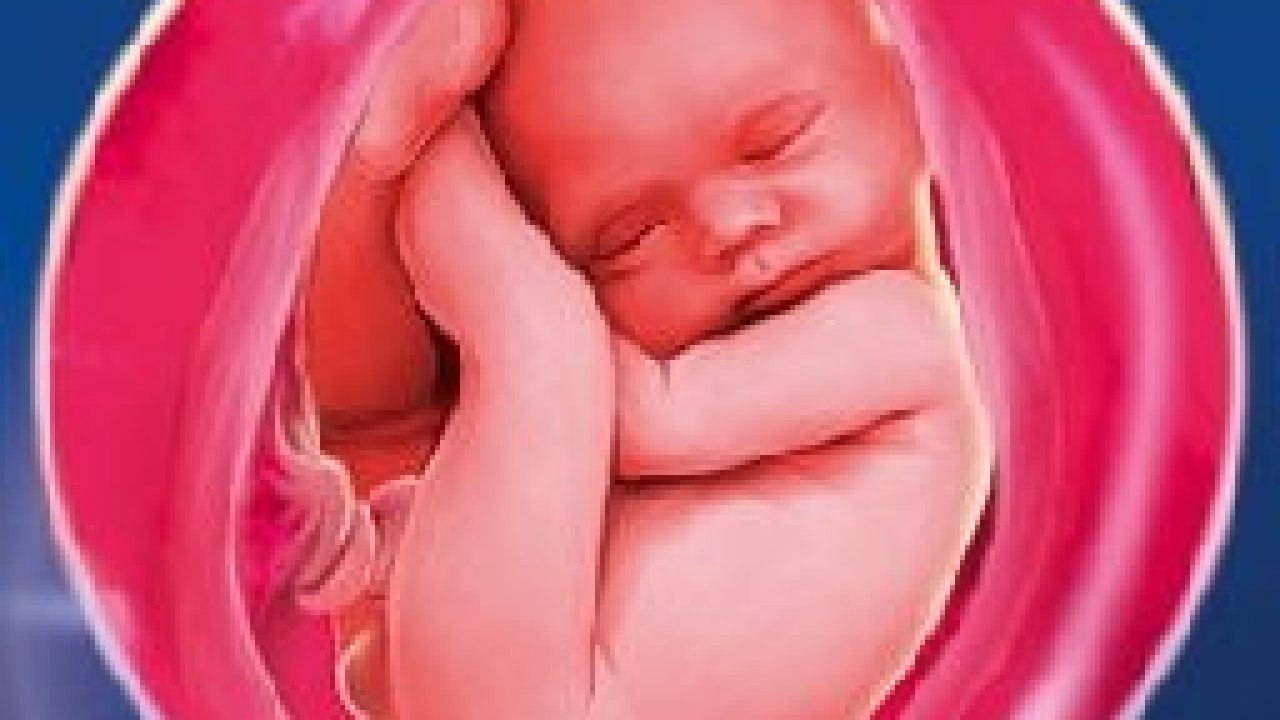

Плод 39 Недель Фото

Плод 39 Недель Фото 100 фото